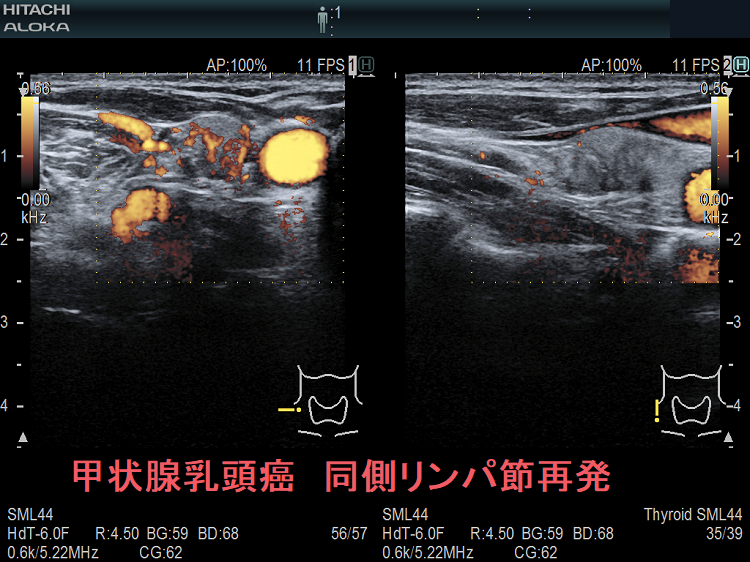

甲状腺乳頭癌鎖骨上窩リンパ節転移再発

甲状腺乳頭癌のリンパ節再発 右鎖骨上窩 超音波(エコー)画像 ドプラーモード

甲状腺乳頭癌のリンパ節再発 右鎖骨上窩 ドプラーモード;内部に異常な走行の血管を認め、血流豊富。

甲状腺乳頭癌のリンパ節再発 右鎖骨上窩 超音波(エコー)画像 ドプラーモード(拡大)

甲状腺乳頭癌のリンパ節再発 右鎖骨上窩 ドプラーモード(拡大);内部に異常な走行の血管を認め、血流豊富。